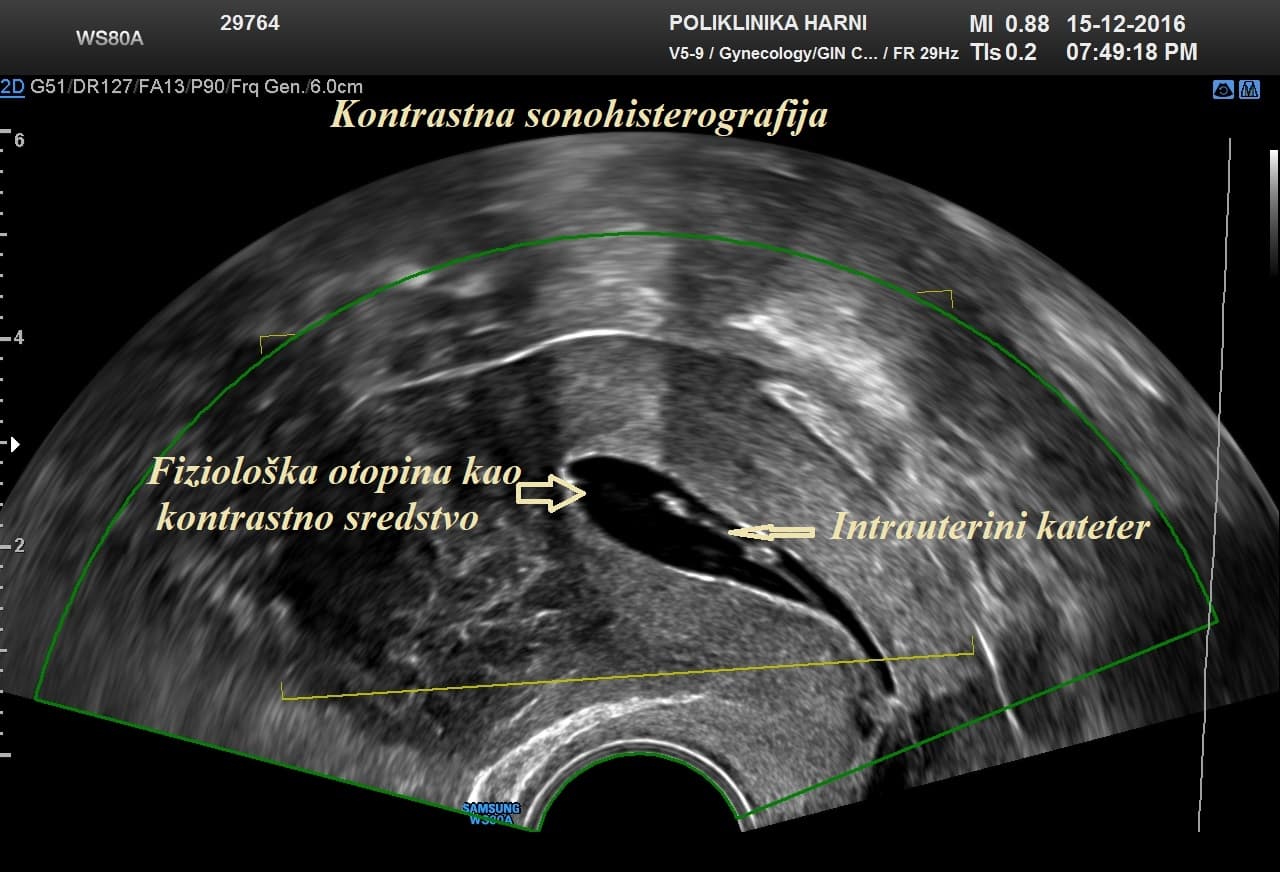

Kontrastni ultrazvukobojenim doplerom i 3D ultrazvukom / Hy-Co-Sy - hysterosalpingo-contrast-sonography sigurna je i učinkovita dijagnostička metoda u procjeni prohodnih jajovoda i od presudnog značenja u obradi neplodnih pacijentica. Provodi se u prvom dijelu menstruacijskog ciklusa nakon potpunog prestanka menstruacijskog krvarenja. Nakon pripreme pacijentice, u kanal vrata maternice se uvodi kateter i ubrizgava kontrast, a potom se prikazuju maternična šupljina, strukture unutar nje, eventualne anomalije maternice i prohodnost jajovoda. Kontraindikacije su trudnoća, krvarenje, akutna zdjelična upala i adneksalni tumor.

Pojava više-dimenzionalnog ultrazvuka omogućuje vizualizaciju ne samo određenih dijelova uterusa nedostupnih dvodimenzionalnom prikazu uslijed položaja uterusa, već i odabir optimalne ravnine kao i načina prikaza sumnjive lezije, a kod 5D ultrazvuka tehnološke inovacije omogućuju dodatne automatske presjeke koji omogućuju slojevitiju sliku i daju dubinu slici ujedno poboljšavajući dijagnostičku točnost. U dijagnostici anomalija uterusa trodimenzionalna rekonstrukcija ima prednost nad dvodimenzionalnim prikazom, te se njegova točnost može mjeriti s točnošću histerosalpingografije.